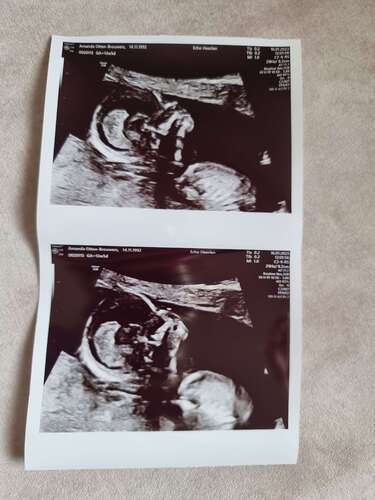

Gister onze 13 weken echo gehad met 14+2. Alles was gelukkig goed. En bij t ...